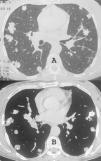

Mujer de 53 años con antecedentes de disnea progresiva en los últimos 3 meses, así como dolor persistente sin irradiación en la región lumbar. También informó de pérdida de peso de 15kg durante el año anterior. En el muslo derecho se observaron lesiones púrpuras indoloras. Los demás resultados de la exploración física y de los análisis de laboratorio no presentaban hallazgos reseñables. La radiografía de tórax y la TAC mostraron múltiples nódulos en los lóbulos pulmonares, de tamaño variable (entre 5 y 25mm), que contenían calcificaciones (fig. 1). Las zonas inferiores del pulmón eran las más afectadas. No se apreciaron linfadenopatía ni derrame pleural. Se observaron asimismo lesiones hepáticas hipodensas y lesiones osteolíticas en las vértebras de la columna vertebral, indicativas de metástasis. Un nódulo resecado mediante biopsia de pulmón a cielo abierto permitió establecer el diagnóstico de hemangioendotelioma epitelioide. La biopsia de la lesión del muslo confirmó la misma histología.

En la radiografía o la TAC torácicas, la HEP se manifiesta como nódulos perivasculares múltiples que presentan márgenes bien o mal definidos y distribución bilateral2,3,5. A pesar de que la histopatología revela con frecuencia calcificación y osificación, la radiología convencional rara vez muestra la densidad cálcica3. La TAC evidencia por lo general más nódulos que los apreciados en la radiografía de tórax, con una distribución perivascular y márgenes irregulares2,3. Nuestra paciente presentaba múltiples nódulos calcificados de tamaño variable. El diagnóstico diferencial incluye las metástasis calcificadas, la amiloidosis nodular, las enfermedades granulomatosas infecciosas, los granulomas hialinizantes, los hamartomas múltiples, los condromas múltiples y la neumoconiosis4,6. Por lo general se requiere una biopsia de pulmón a cielo abierto para establecer el diagnóstico. La inmunohistoquímica también suele ser necesaria para el diagnóstico1. En conclusión, la HEP debe considerarse en el diagnóstico diferencial de nódulos calcificados múltiples.